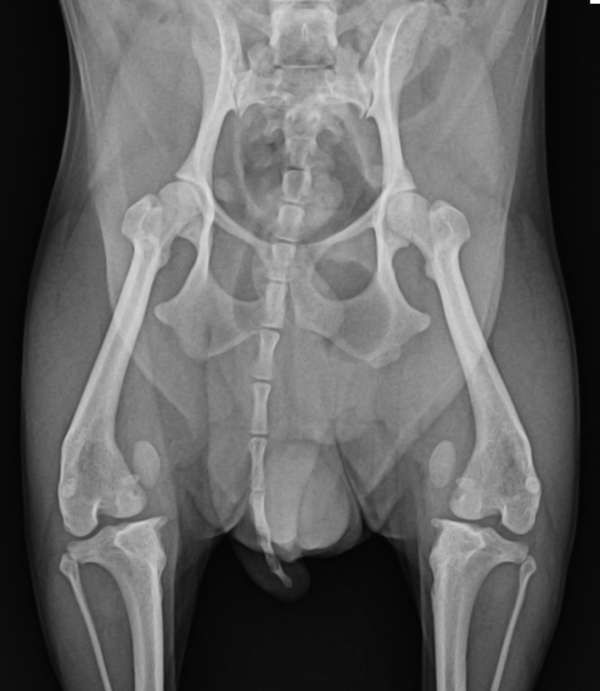

무릎관절은 대퇴뼈와 정강뼈가 경첩처럼 접히고 펴지는 모양으로 관절운동을 하게 됩니다. 슬개골(무릎뼈)은 독립되어 있는 아주 작은 뼈이지만 무릎관절의 기능 및 안정성에 큰 기여를 하는 중요한 구조물입니다. 대퇴뼈 고랑 위에 위치하여 무릎관절이 일직선 상에서 원활하게 운동할 수 있게 해줍니다.

슬개골 탈구란 정상적으로 대퇴고랑 안에 위치해야 할 슬개골이 안쪽 혹은 바깥쪽으로 빠지는 질환을 의미합니다.

또한 대퇴고랑이 적당한 깊이로 형성되어 있지 못해 슬개골을 담아주지 못하고 얕아져 있는 경우 슬개골이 쉽게 빠질 수 있게 됩니다.